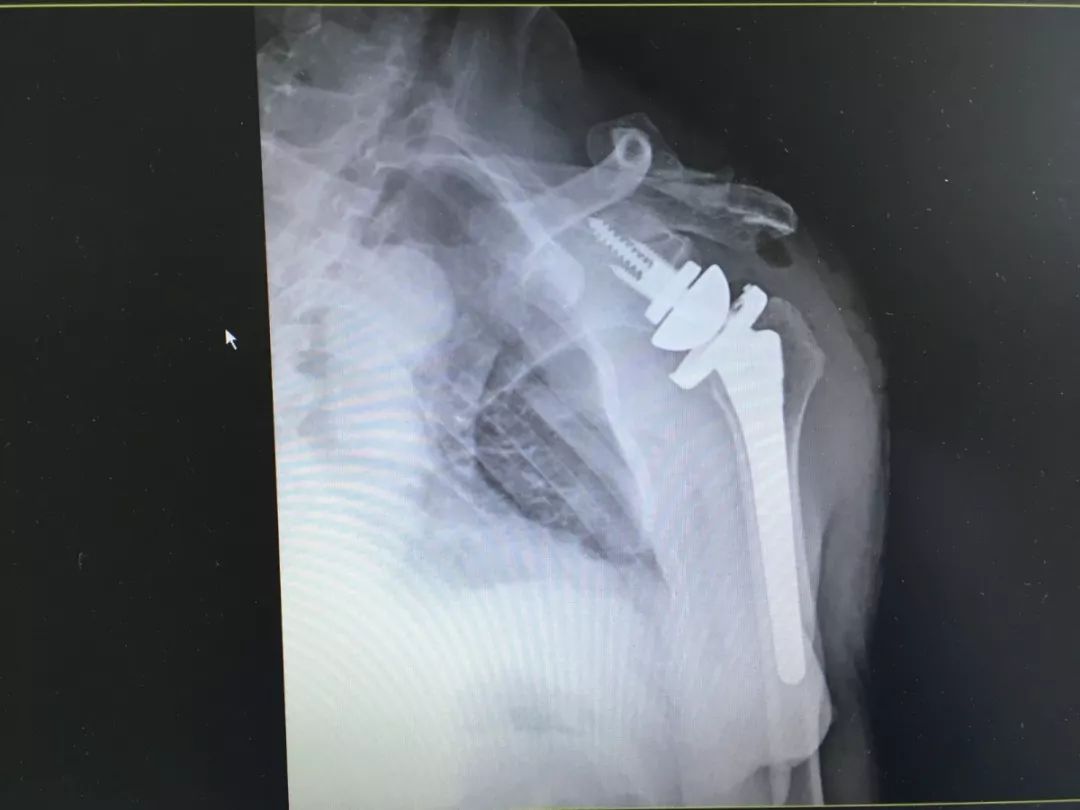

肩关节粉碎性骨折

「反式全肩关节置换」手术后